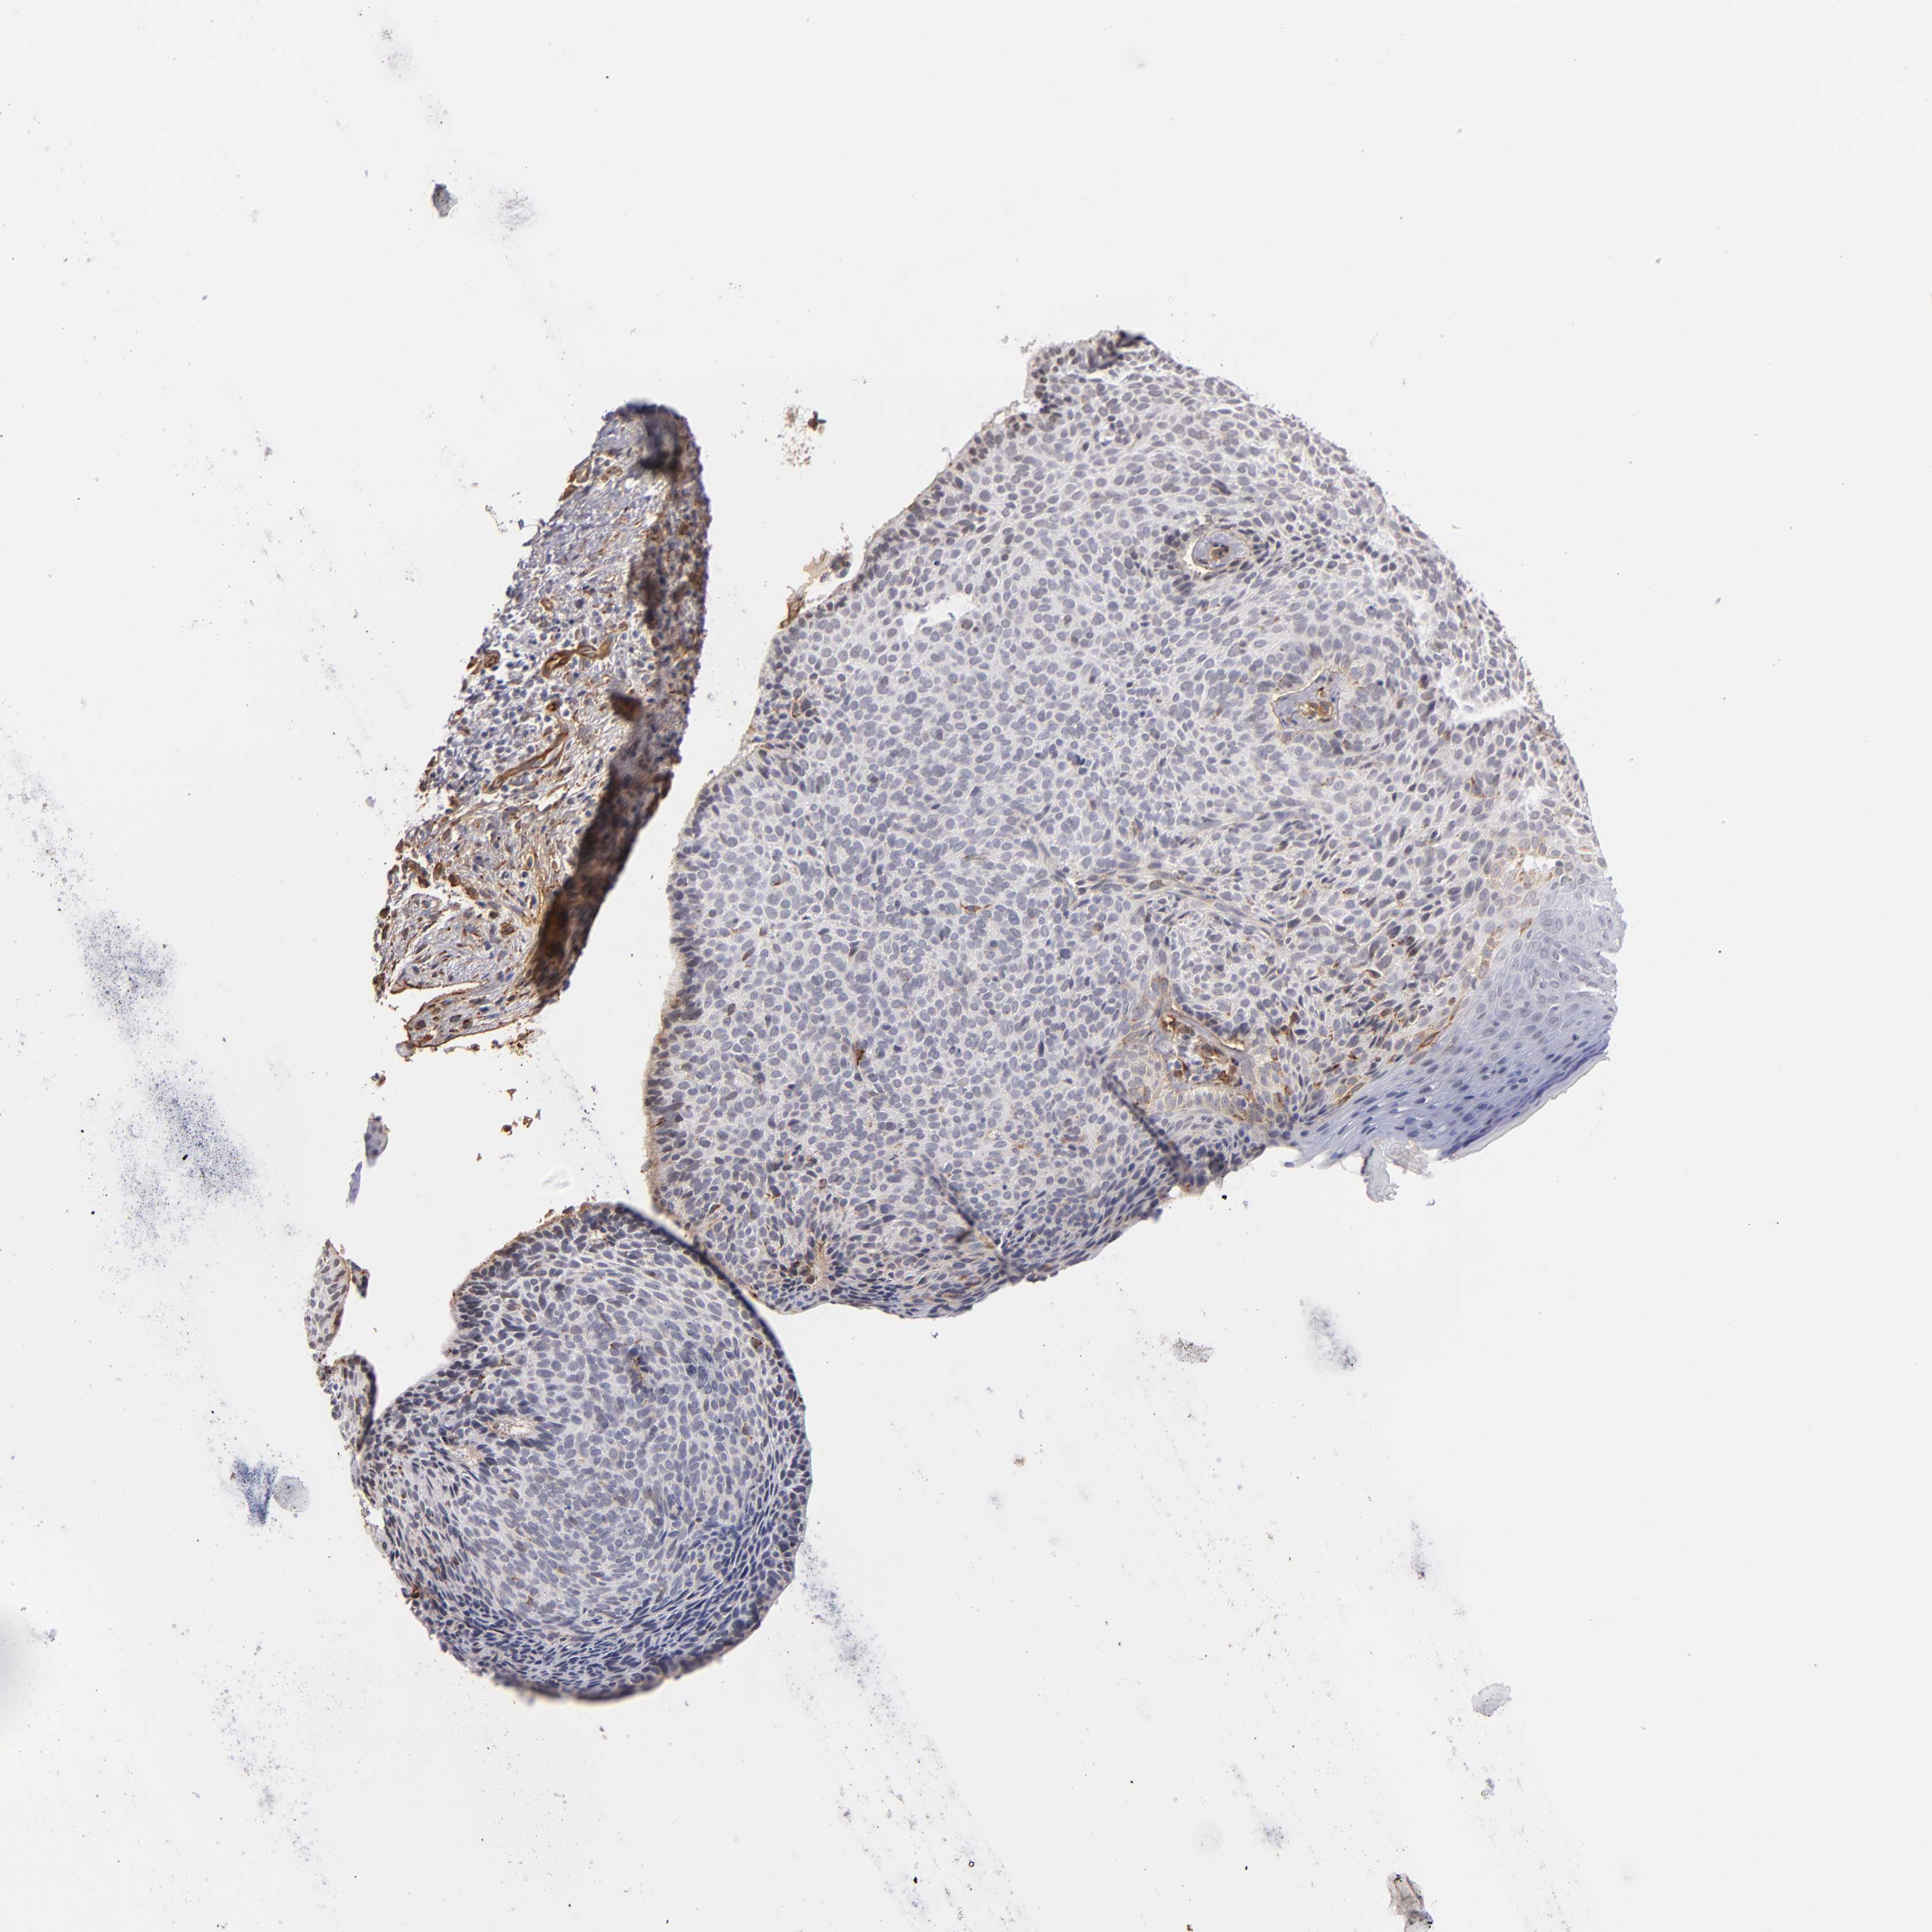

Basal cell and squamous cell cancer

SKIN CANCER - Protein expressioni

A mouse-over function shows sample information and annotation data. Click on an image to view it in a full screen mode. Samples can be filtered based on level of antibody staining by selecting one or several of the following categories: high, medium, low and not detected. The assay and annotation is described here.

Antibody stainingi

Antibody staining in the annotated cell types in the current human tissue is reported as not detected, low, medium, or high, based on conventional immunohistochemistry profiling in selected tissues. This score is based on the combination of the staining intensity and fraction of stained cells.

Each image is clickable and will lead to virtual microscopy that enables deeper exploration of all samples and also displays staining intensity scores, fraction scores and subcellular localization as well as patient and tissue information for each sample.

Antibody HPA001908

Antibody HPA001909

Antibody CAB004486

Antibody CAB078163

Squamous cell carcinoma, NOS

Basal cell carcinoma